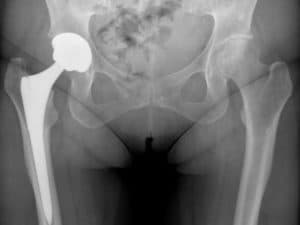

Thinning and roughening of the smooth cartilage that lines the joint surfaces. Gradually occurs with age, but can start early if there is an issue with the shape of the joint. Best managed with exercise to keep strong and mobile along with keeping weight down. More advanced cases may eventually need surgery to replace the joint.

Keyhole surgery has been proven to be very effective, especially for young adults with impingement, where the aim is to relieve symptoms and reduce the chance of early wear and tear in the future. When needed, hip replacements are truly remarkable allowing people to get back to painfree exercise and they can last a lifetime (not just ten years as some people still think!). With younger people having hips replaced who want to return to sport and work, the need for better rehab has increased. Just getting back to walking is not good enough for many people and we take great pleasure in helping people get back to the activity and exercise they love.